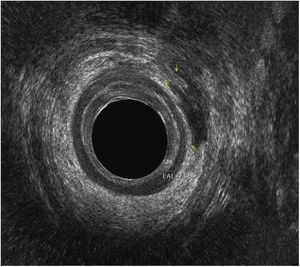

The patient is a 61-year-old male with a perianal trauma injury caused by a bull horn. The examination was performed under anesthesia to rule out secondary lesions, and a perianal incision/contusion wound was observed close to the sphincter apparatus (Fig. 1). Upon digital rectal examination, no disruptions of the rectal wall were palpable, and rectoscopy ruled out complete mucosal lesions. The study was complemented with endoanal ultrasound to assess sphincter integrity, demonstrating an ascending left pararectal path with laceration of the external anal sphincter (less than 50°) in the middle anal canal (arrows), and complete integrity of the internal anal sphincter (Fig. 2). Due to the septic characteristics of the lesion and its grade (Grade IIIa), we decided not to perform primary sphincter repair, and the surgery was completed with extensive debridement and thorough irrigation. The patient was discharged 48h later. During follow-up, he presented no changes in continence. We conclude that intraoperative endoanal ultrasound is a useful tool for the evaluation of sphincter defects after perianal trauma.